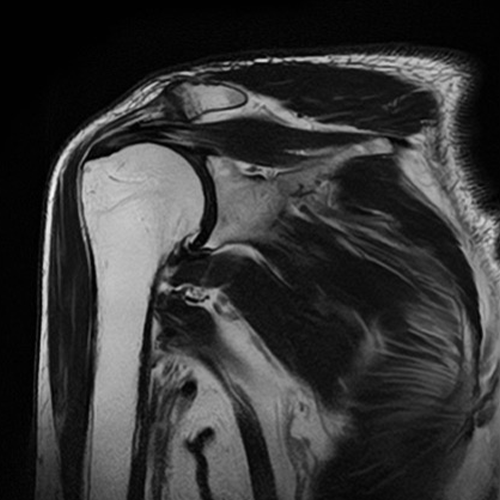

MRI検査

装置の紹介

当院では1.5テスラ キヤノンメディカルシステムズExcelart Vantage (MRT-2003)を用いています。

この装置は撮像時の騒音が従来装置に比べ約90%低減されています。また、検査架台の長軸が短縮され解放的でリラックスして検査を受けることができます。

MRI検査とは

CTやX線検査と違い、磁石と電波を使って体の様々な断面像を撮像するので、放射線による被ばくはありません。

造影剤を使用せずに血管を描出することもでき、脳動脈瘤や血管狭窄などの診断に利用されます。また、胆管・膵管・脊髄・尿路なども非造影で検査を行うことができます。

頭部検査においては、特に有用で、CT検査では発見できない急性期の脳梗塞を捉えることができ、早期診断・早期治療を可能にします。この他にも、脊椎・骨軟部・関節・腹部・骨盤腔(子宮・卵巣・前立腺)の病変に優れた描出能があり、様々な疾患の早期発見・診断に有用とされ、研究が進んでいます。

全身DWI

頭部

脳血管像(非造影)

胆管・膵管(非造影)

腹部

乳房DWI